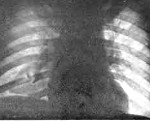

• Рентгенографии или КТ лёгких. Участки инфильтрации лёгочной ткани, соответствующие зоне ушиба, определяются на рентгенограмме через 24-48 часов от момента травмы. Рентгенография позволяет выявить пневмо- и гемоторакс, повреждение костного каркаса. При тяжёлой травме органов дыхания предпочтительнее выполнить компьютерную томографию. Она помогает определить наличие пневмоцеле, ателектазов, отдифференцировать ушиб от разрыва лёгкого.